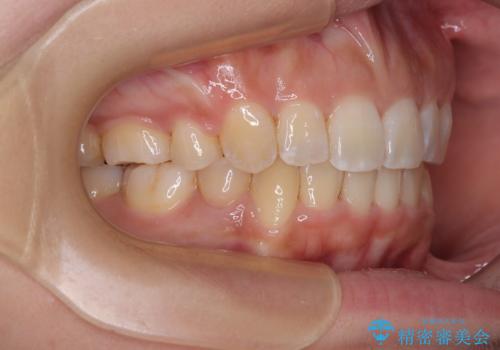

八重歯と上顎前突 ワイヤー装置での抜歯矯正

- 八重歯と、上下前歯が接触しないくらい前突した前歯を気にして来院された患者様です。

奥歯の噛み合わせは正常に近い状態でしたが、右上の奥歯に突起があったり、上下前歯が非接触であったりしていたため、補助装置を使用して上顎前歯を積極的に引っ込めるように計画しました。

口元の突出感を改善するために上下左右の小臼歯4本を抜歯し、ワイヤー装置によりデコボコを解消しながら口元の突出感も改善していくこととしました。

上下の前歯が接触する仕上がりとなったので、横顔の印象が大幅に改善されました。